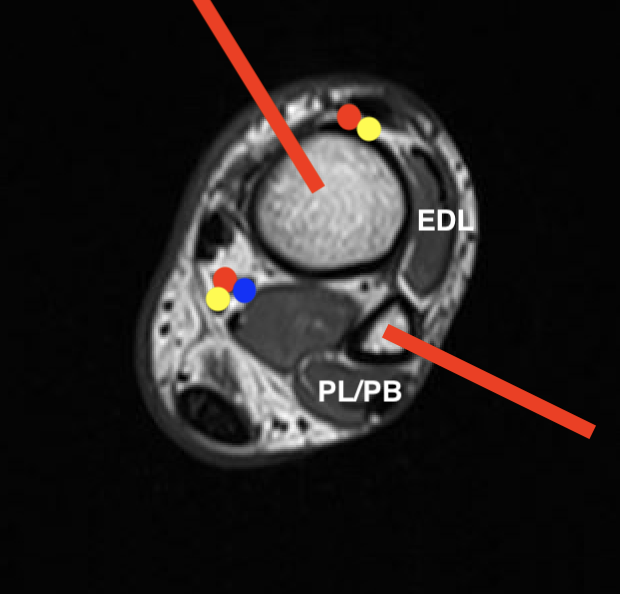

Foot

Navicular / Medial cuneiform Direct medial

Cuboid Direct lateral

Intermediate cuneiform

Between EHL and EDC

Away from dorsalis pedis

Lateral cuneiform Lateral to EDC

Metatarsals / phalangeals Dorsal approach

Soft tissue tumour Medial or lateral as required